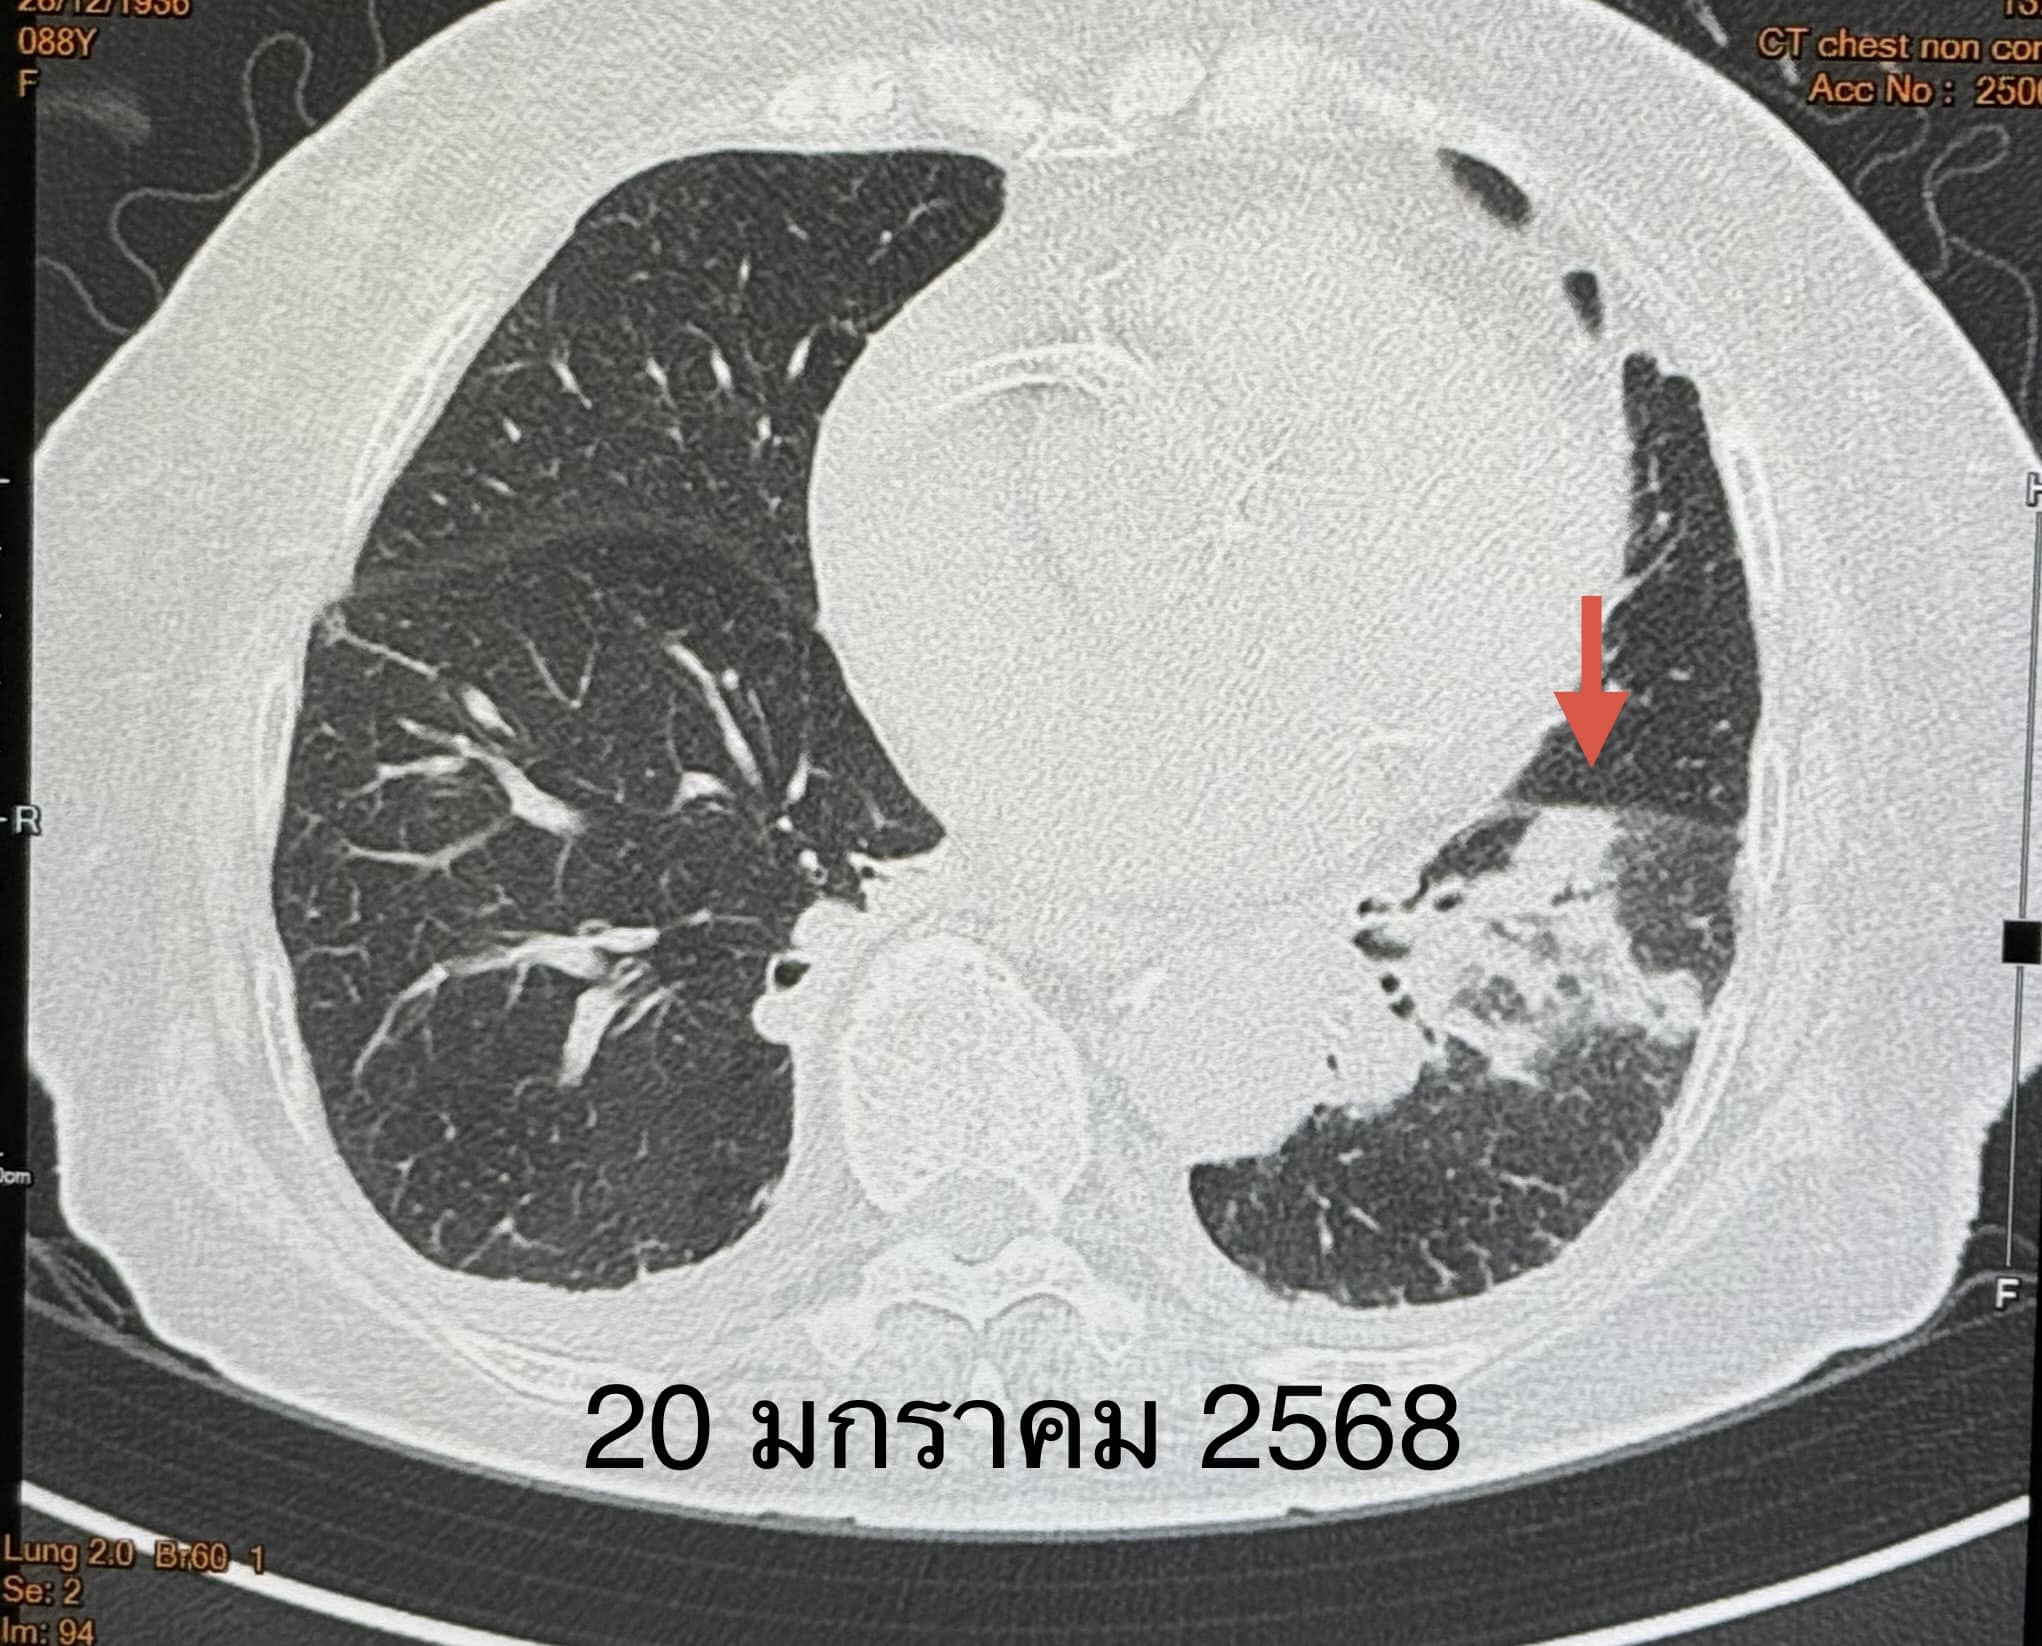

“ตรวจร่างกาย ระดับออกซิเจนที่ปลายนิ้วต่ำ 87% ต้องให้ออกซิเจน 2 ลิตร/นาที ไม่มีไข้ ฟังปอดมีเสียงผิดปกติเล็กน้อยที่ปอดข้างซ้ายด้านล่าง เจาะเลือด เม็ดเลือดขาวในเลือดปกติ เอกซเรย์ปอดมีฝ้าขาวในปอดข้างซ้ายด้านล่าง (ดูรูป) ทำคอมพิวเตอร์ปอดยืนยันว่ามีฝ้าในปอดข้างซ้ายด้านล่าง และมีน้ำในช่องเยื่อหุ้มปอดเล็กน้อย (ดูรูป) ตรวจเลือดเม็ดเลือดขาวปกติ แยงจมูกส่งตรวจรหัสพันธุกรรมเชื้อ 22 สายพันธุ์ไม่พบเชื้อ ส่งเลือดตรวจ Legionella pneumophila Antibody IgM positive 1:200”

“วินิจฉัย: ติดเชื้อแบคทีเรียลีจิโอเนลลา นิวโมฟิลา Legionella pneumophila ทำให้ปอดอักเสบ ให้ยา azithromycin และ levofloxacin คนไข้ดีขึ้น ไม่ไอ ไม่เหนื่อย ระดับออกซิเจนปกติ ไม่ต้องใช้ออกซิเจน วันที่ 26 มกราคมเอกซเรย์ปอดกลับมาเป็นปกติ (ดูรูป)”